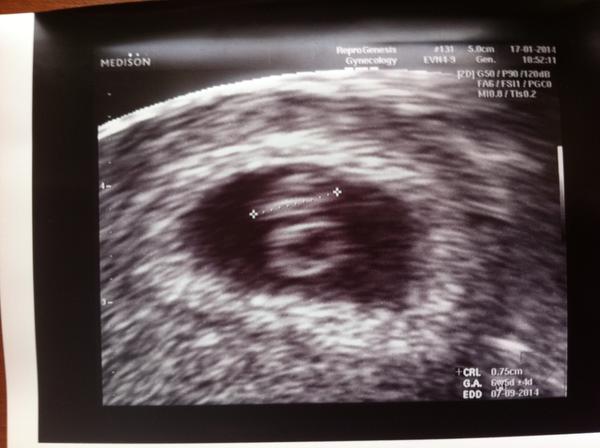

Bola som na tejto klinike 2x na KET a môžem Vám ju vrelo odporučiť. Konzultácie emailom a telefonicky, všetky merania som absolvovala u svojho gynekológa. Vycestovali sme len na vklad. Je tu super personál o ktorom sa nám na Slovensku môže len snívať. Vychádzajú maximálne v ústrety a hlavne prídu na príčinu Vašich neúspechov. Hlavne by som chcela vyzdvihnúť ich ochotu riešiť Váš problém, kým na SK ste zdroj peňazí tu ste hlavne ich pacient. Odpovedajú na Vaše otázky, vždy dobre poradia a úprimne sa tešia z Vášho úspechu. Klinika je na ul. Hlinky 144 Brno cca 150 m od Reprofitu. Boli sme úspešní a čakám miminečko 🙂 je to úžasný pocit, ktorý doprajem každej jednej snažilke 🙂

Tak nevzdavajte to, urcite to stoji za vsetko drzat v naruci ten vytuzeny uzlik 🙂 ti je nas maly Reprogenesisak 🙂